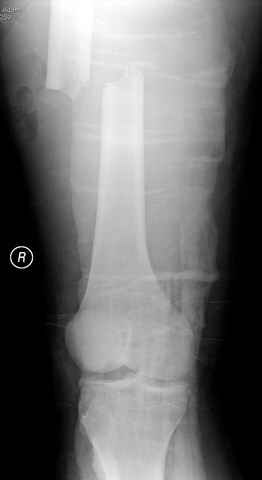

По поводу открытого перелома больной ургентно взят на ретроградное интрамедулярное штифтование, после рутинного дебрайдмента и фасциотомии на бедре и на голени.

перелом бедра

постоперационные